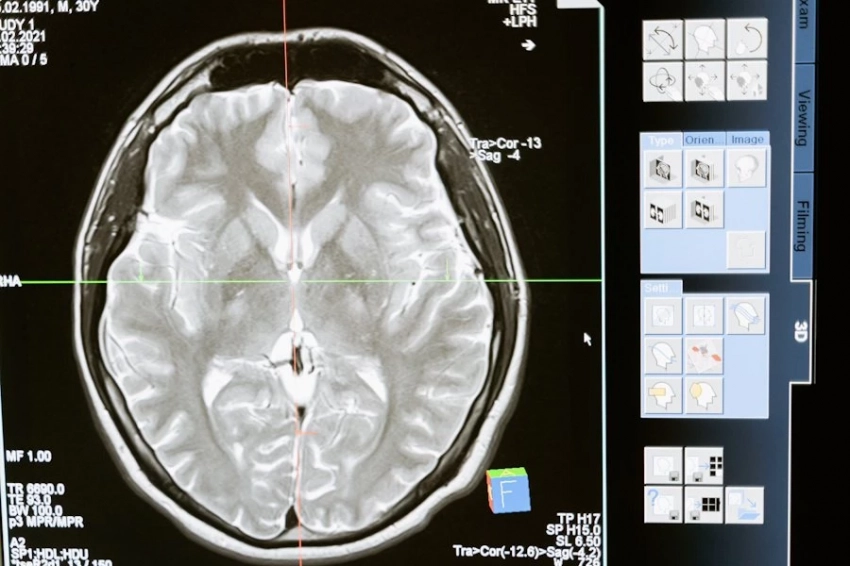

Группа Папалео выявила решающую роль префронтальной коры в этих социально-когнитивных процессах. Они провели доклинические тесты и использовали передовые методы для изучения мозговых механизмов, лежащих в основе эмфатического поведения. Их выводы показывают, что определенная группа клеток является ключевым модулятором эмоциональных реакций на других, основанных на эмоциональном опыте себя. Эти нейроны вырабатывают кортиколиберин (CRF), молекулу, участвующую в механизме реакции на стресс, и, по словам исследователей IIT, они функционируют как своего рода эмоциональная память, влияя на реакции на социально-эмоциональные стимулы.